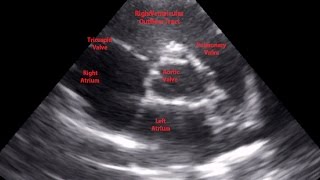

Gulfcoast Ultrasound Institute Instructor Emily Downs, BS, RDMS, RVT, RDCS, RT demonstrates how to evaluate the bifurcation of the aorta at the level of the distal aorta using ultrasound.